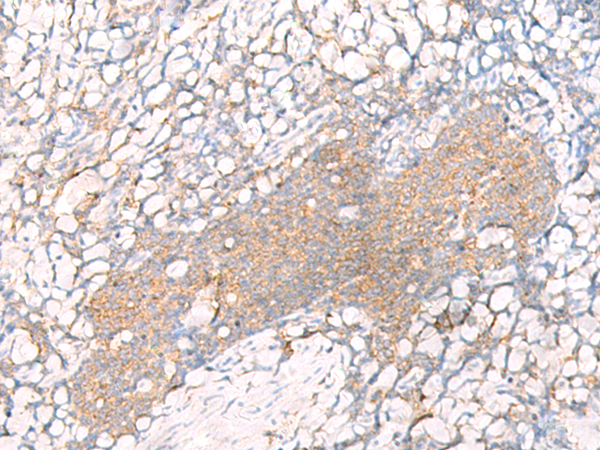

IHC positive control:

Human tonsil

IHC Recommend dilution:

20-100